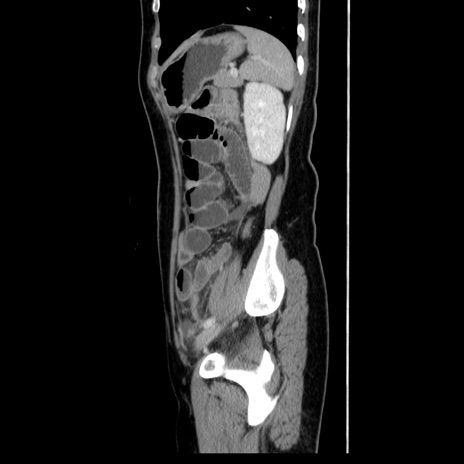

症例39(矢状断像)

【症例】40歳代女性

【主訴】上下腹部痛

【現病歴】2日目から下腹部痛あり。夜間は痛みで眠れなかった。昨日より上腹部痛と下痢が出現。臥位で痛みは軽快したため、休んでいた。本日になって臥位でも立位でも痛みが強くなってきたため救急要請。

【既往歴】子宮内膜症

【身体所見】部:平坦・軟、左上下腹部に圧痛あり、反跳痛あり。

【データ】WBC 21800、CRP 26.78

CT